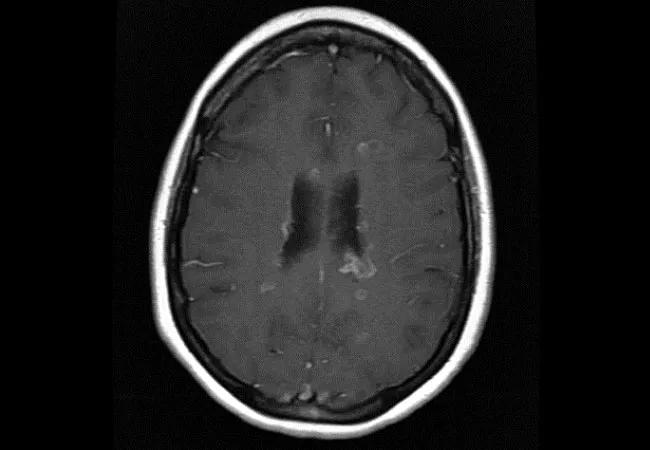

And the findings suggest that fingolimod may hold a few advantages — namely, that patients are less likely to discontinue medication early in the course of treatment and are at lower risk for enhancing MS lesions on brain MRI (Figure) as compared with patients taking DMF. Results also showed that DMF-treated patients tended to relapse earlier compared with fingolimod-treated patients.

Figure. MRIs of the brain showing characteristic lesions of MS (left panel) with associated gadolinium enhancement (right panel) consistent with active inflammatory disease activity.

• DMF recipients had nearly three times the number of gadolinium-enhancing lesions on MRI (odds ratio [OR] = 2.90 [95% CI, 1.24-6.57]), indicating that their illness was less well-controlled